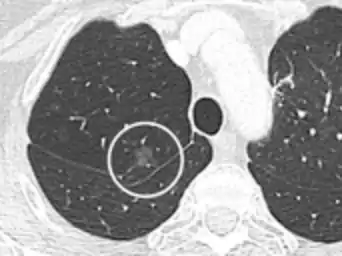

Lung nodule abutting a pulmonary cyst.[9]

• A lung nodule abutting a pulmonary cyst is a rare finding, yet indicating cancer.[9]